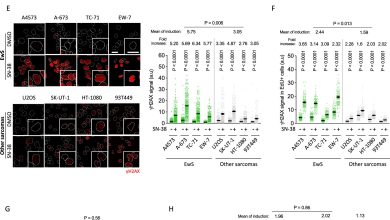

Novo mecanismo está subjacente à sensibilidade da quimioterapia no câncer ósseo agressivo

As linhas celulares e tumores EwS são altamente sensíveis aos venenos TOP1. Crédito: Oncogene (2025). DOI: 10.1038/s41388-025-03496-9 Uma equipa de…

Ler Mais » - Notícias